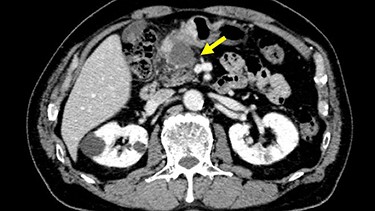

Chest and abdominal computed tomography (CT) showed no distant metastasis, but the tumor of the antrum was clearly visualized and was located close to the pancreatic head (Fig. 1). EGD revealed a large ulcerated lesion at the greater curvature of the antrum (Fig. 2). Hematoxylin and eosin staining of the biopsy specimen of the tumor confirmed a well-differentiated adenocarcinoma (tub1, tub2) (Fig. 3). The assessment of the HER2 expression by immunohistochemistry revealed the overexpression of HER2 (3+) in the biopsy tissue of the gastric tumor (Fig. 4).

Abdominal CT showed the tumor at the gastric antrum visualized as a thickened wall, suggestive of direct invasion to the pancreatic head (arrow).